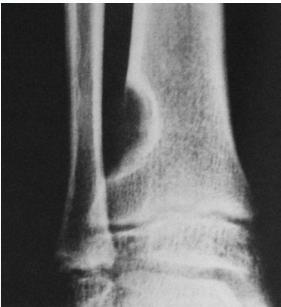

Simple Bone Cyst

- Solitary – unicameral

- Children

- Metaphysis:

- Prox. Humerus and Femur

- Not a tumor:

- Not seen in adults

- Heals spontaneously

- Pathological fracture / or incidental

- Aspirate is clear straw-colored

Sources: www.juniorbones.com, Orthopedic Radiology. A Greenspan. Lippincott-Raven

Source: https://radiopaedia.org

Treatment

- Small, reducing in size:

- Leave alone

- Increasing in size, active:

- Moderate trial of bone marrow injection

- Large (risk of fracture) Curettage & grafting

- Pathological fracture:

- Treat fracture

- Cyst might heal

- Recurrent / injection failed:

- Surgical curettage and bone grafting

Sources: https://www.sciencedirect.com/science/article/pii/S1877056814003338, Orthopedic Radiolgy. A Greenspan. Lippincott-Raven